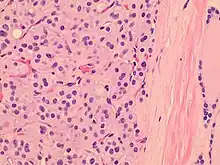

Histopathology of a Hürthle cell adenoma

Hürthle cells are characterized as enlarged epithelial cells. These cells, when stained with hematoxylin-eosin show as pink. This is due to the abundant mitochondria and granular eosinophilic matter within the cells' cytoplasm. These cells are often found in the thyroid. The thyroid is a butterfly-shaped organ, responsible for producing various hormones for metabolism. These cells are often benign, but they can be malignant and metastasize. Hürthle cells are resistant to radiation, but can be treated using radioactive iodine treatment.[4]